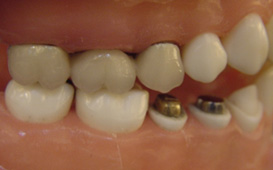

缺牙導致牙齒移位 - 臨床實例一

缺牙導致牙齒移位 - 臨床實例二

上面的牙往下墜,下面的牙往上長,前面的牙往外飆 – 咬合崩塌牙周病,蛀牙;這些現象必然發生,時間越久,問題越大,而且除非藉由矯正及其他牙科治療,無法修正。